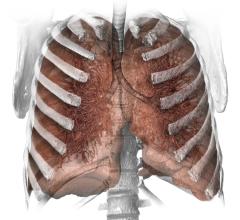

March 27, 2015 — Adding two non-invasive imaging tests to traditional cardiovascular disease risk factor assessment…